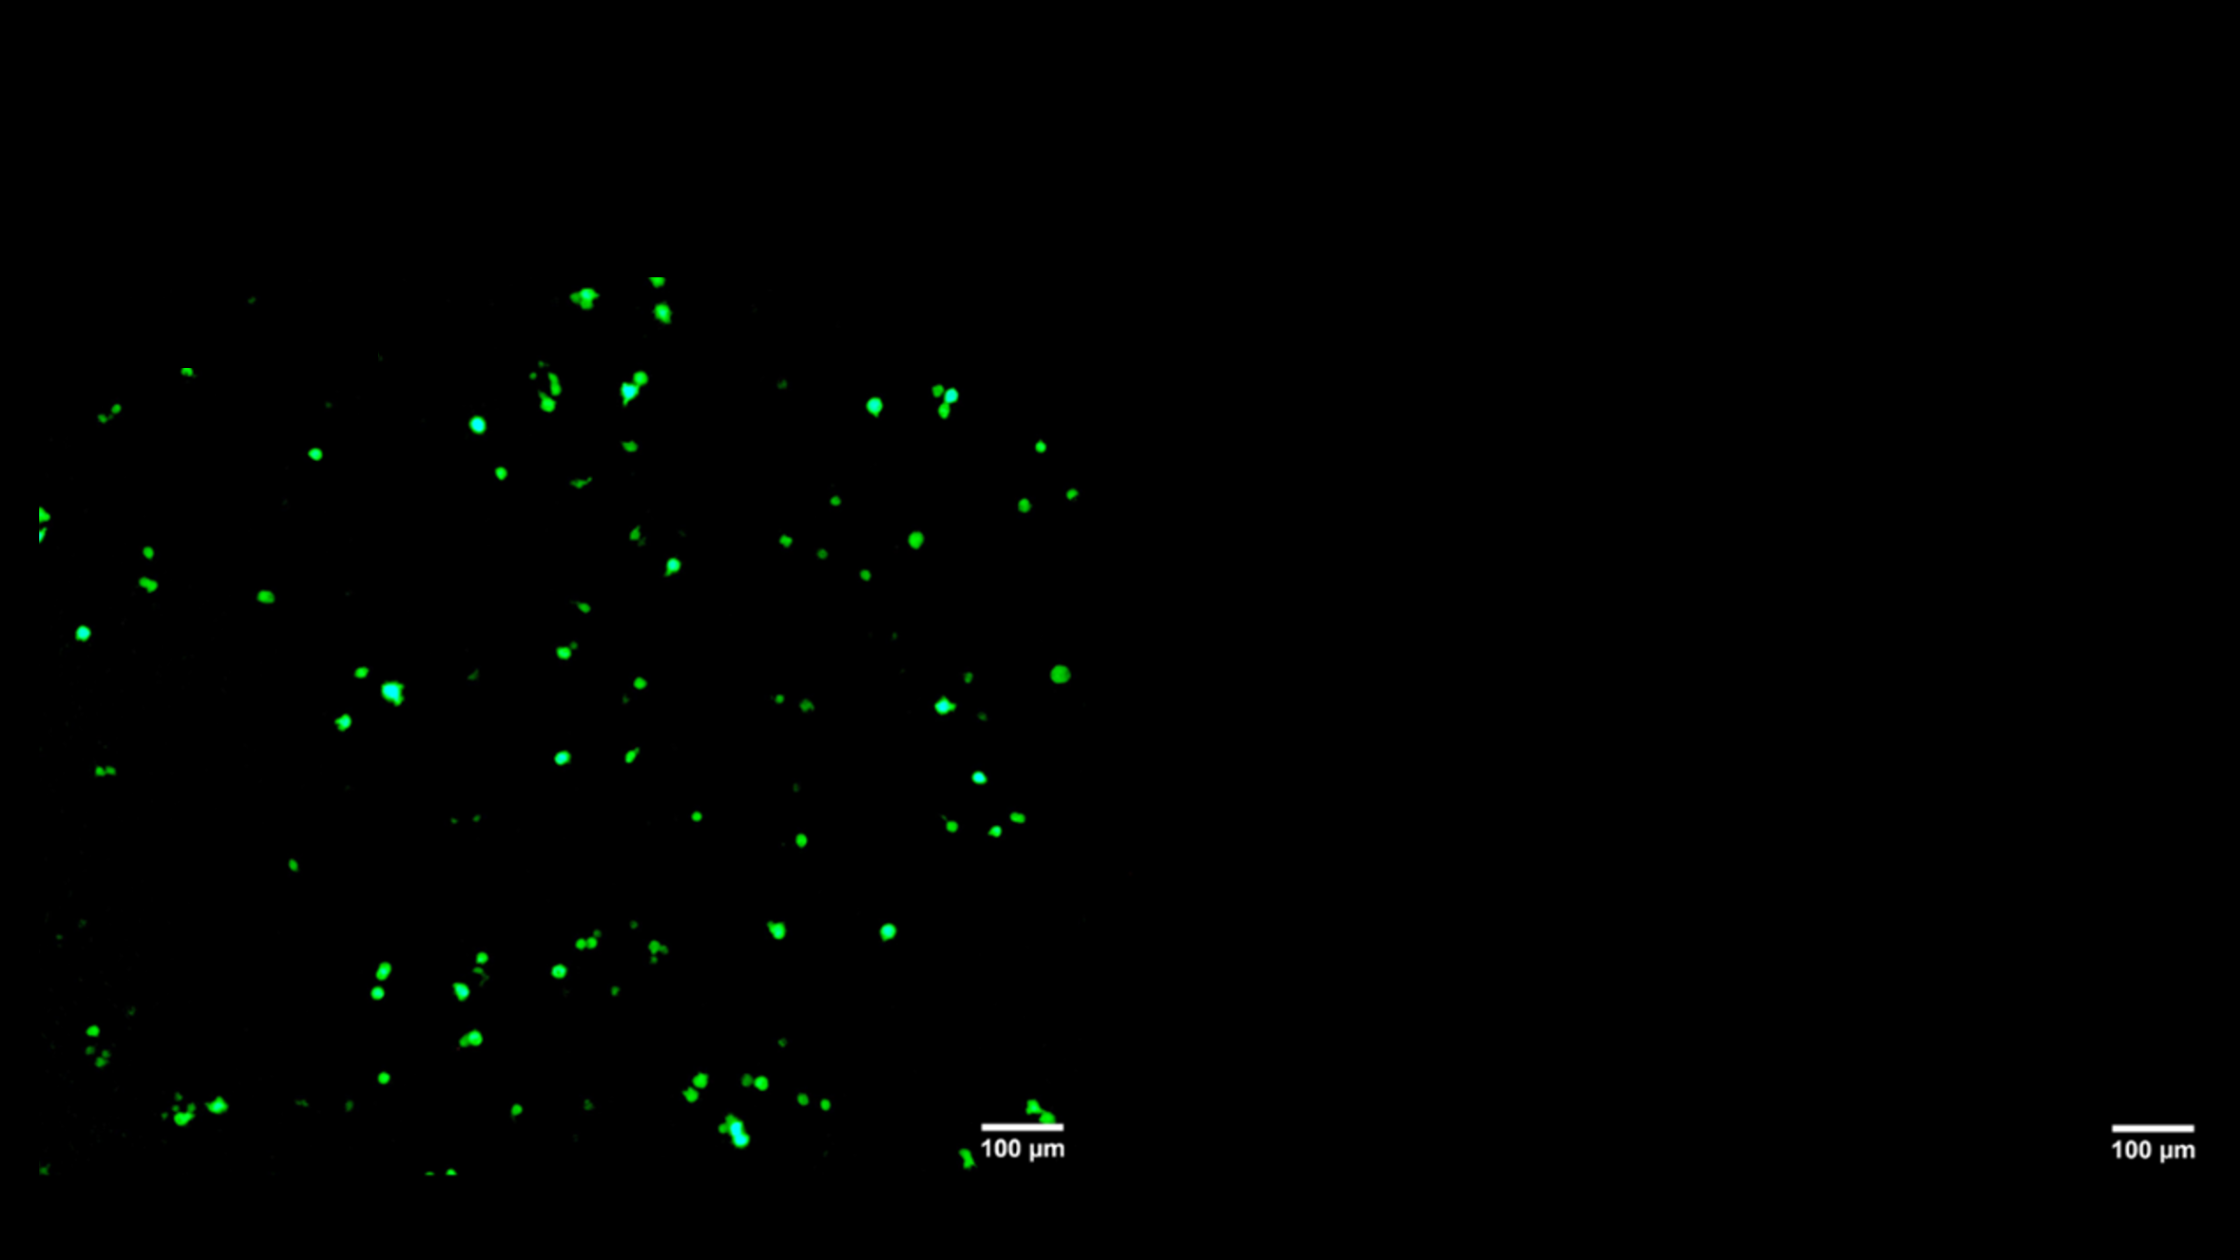

After storage, mRNA delivered with NanoVac (left) was effectively transfected while mRNA delivered using standard lipid nanoparticles (LNPs) (right) was not.